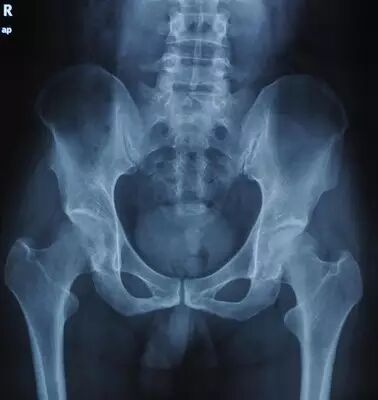

股骨头坏死,是指由于股骨头微循环障碍导致股骨头缺血、结构改变、股骨头塌陷、关节功能障碍的骨关节疾病。

股骨头坏死可以根据病情,由轻到重分为六期,不同的时期有不同的治疗方法。

0期病人有髋部症状,但是X线片与磁共振正常

I期病人有髋部症状,X线片正常,磁共振出现异常

II期病人有髋部症状,磁共振出现异常,X线片显示股骨头出现透光和硬化改变

III期磁共振出现异常,X线片显示软骨下塌陷(新月征),股骨头内出现空洞,股骨头没有变扁

IV期X线片显示股骨头变扁

V期X线片显示关节狭窄或髋臼病变

VI期严重退行性改变